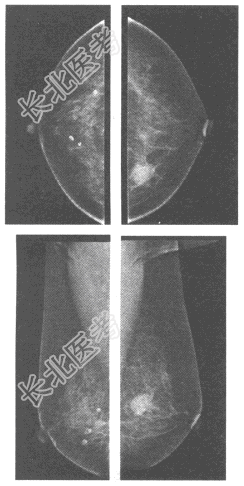

- 单项选择题女,58岁, 发现左侧乳腺肿块,质硬, 与周围组织分界不清,乳腺钼靶X线图像如下, 左侧乳腺的病变最可能的诊断为

A、乳腺腺病

B、乳腺癌

C、乳腺纤维腺瘤

D、乳腺炎

E、乳腺囊肿